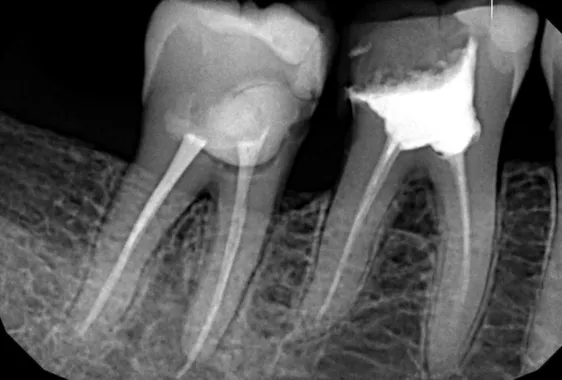

Прицельный снимок (радиовизиография)

Рентген конкретного участка необходим для уточнения диагноза и более контролируемого лечения, например, если нужно установить положение корней конкретного зуба мудрости относительно других зубов в ряду. Снимок выполняется методом радиовизиографии. Полученное изображение снимается датчиком и передается на компьютер. Врач будет иметь доступ к результатам обследования в любой момент. Рентген зубов Киев, сделанный в нашей стоматологии, сохраняется в цифровой карточке пациента и может быть отправлен на цифровой носитель.